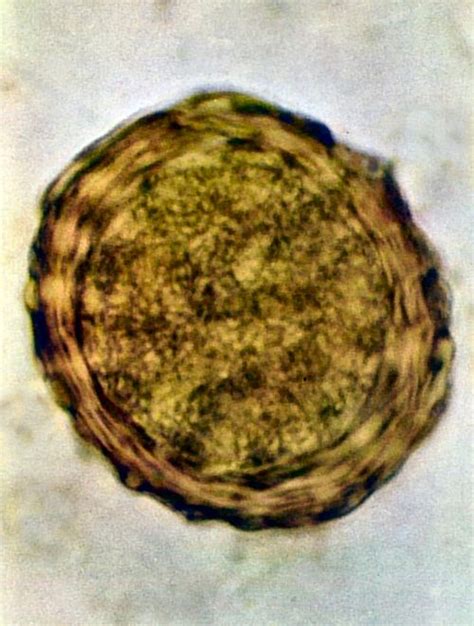

Medzi najčastejšie jednobunkové parazity, ktoré spôsobujú črevné infekcie, patria kokcídie a giardie. Sú také malé, že ani dospelé jedince voľným okom v truse neuvidíme. Bežné odčervovacie prípravky na tieto parazity nezaberajú. Pri hnačkách, obzvlášť u šteniatok alebo mačiatok, je preto potrebné myslieť aj na možnú infekciu týmito druhmi parazitov. Veterinár vám odporučí koprologické vyšetrenie, teda vyšetrenie trusu. Aby bolo vyšetrenie čo najpresnejšie, veterinár vám odporučí zbierať vzorku stolice 3 alebo aj 5 po sebe nasledujúcich dní. Pri vyšetrení stolice z viacerých dní je väčšia šanca zachytiť vajíčka parazitov. U škrkaviek a pásomníc hľadáme v truse vajíčka, pri kokcídiách a giardiách hľadáme ich cysty. Práve vajíčka a cysty sú infekčné, ich požitím sa zviera nakazí. Cysty giardií je obzvlášť ťažké zachytiť, pretože sa vylučujú nepravidelne, preto je možné, že vám veterinár odporučí aj iné testy na vylúčenie/potvrdenie infekcie giardiami. Nie je vôbec zriedkavé, že aj v truse odčervovaných zvierat veterinár odhalí vajíčka škrkaviek alebo pásomníc.

Klinická kokcidióza sa vyskytuje najčastejšie u šteniatok. Častými kokcídiami u psov a mačiek sú: Isospory - spôsobujú hnačky u šteniatok a mačiatok najmä do veku 3-4 mesiace. Vývoj a množenie kokcídií prebieha v tenkom čreve, kde spôsobujú zápal. Príznakmi sú apatia, nechutenstvo, horúčka, krvavé hnačky, dehydratácia. Neospory - infekcia spôsobuje pôrody málo životaschopných šteniat, parézy, paralýzy panvových končatín. Medzihostiteľom sú bylinožravci, definitívnym hostiteľom je pes. Prenos je cez placentu do plodu. Fenka môže prenášať parazita aj niekoľko vrhov po sebe. Príznakmi sú sťažené prehĺtanie, ochrnutie čeľustí, ochablosť svalstva, srdcová nedostatočnosť. Toxoplazmóza - konečným hostiteľom je mačka. Parazit tvorí v bunkách sliznice tenkého čreva oocysty, ktoré sú vylučované trusom najmä u mačiatok medzi 3-8 mesiacmi veku. Príznaky sú najvýraznejšie u mláďat a to zvýšená teplota, zväčšenie lymfatických uzlín, výtok z očí, nosa, zápal mandlí, sťažené dýchanie, hnačky, zápal pľúc. Ak dostane akútnu infekciu žena, ktorá je tehotná a nemá protilátky proti danému ochoreniu, parazit môže infikovať plod a vyvolať potrat alebo poškodenie centrálneho nervového systému. Medzi kokcídie patrí napr. Isospora, Cryptosporidium, Neospora, alebo Toxoplasma. Isospora a Cryptosporidium spôsobujú črevné problémy najmä u šteniatok a mačiatok do 6 mesiacov veku. Častejšie sa objavujú v prostredí, kde je chované väčšie množstvo zvierat, alebo v zhoršených zoohygienických podmienkach. Neospora je parazit psov, spôsobuje neurologické príznaky, k nákaze dôjde pri požití oocysty, ale aj pri prenose od matky počas gravidity. Väčšina kokcídií pre človeka nie je nebezpečná, s výnimkou Toxoplasmy. U Toxoplasmy je definitívny hostiteľ mačka. Najčastejšie sa nakazia mačatá a mladé mačky a k vylučovaniu cýst dochádza iba 1-3 týždne po nákaze. Aby sa človek nakazil, musí dôjsť k požitiu zrelej oocysty - dozrievanie oocysty v truse trvá 2-4 dni, alebo sa človek môže nakaziť nedostatočne tepelne opracovaným mäsom, či zle umytým ovocím a zeleninou. Pri dodržiavaní hygieny a príjme uvareného mäsa je nákaza veľmi málo pravdepodobná.